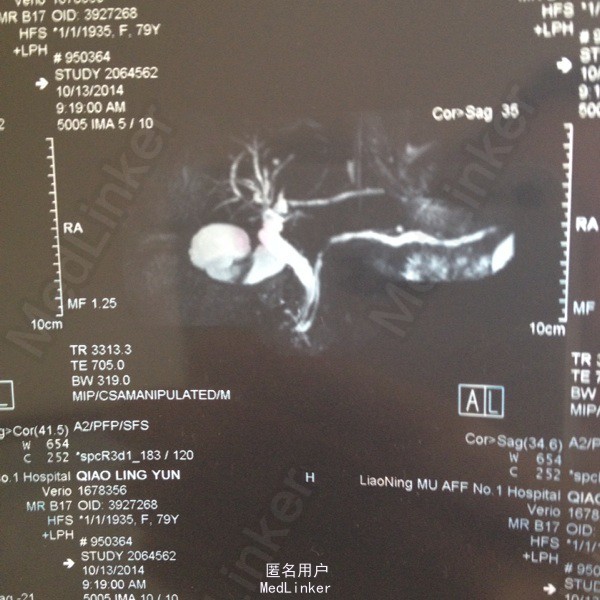

79岁女患,右上腹不适一年。无发热,无噁心及呕吐,无腹泻腹痛。 在普外轮转收集的片子,只有此患者图片,根据此图片回忆的患者病史及查体。时间较长,可能不详尽。

查体:右上腹轻压痛。余未见异常。 MRCP:见图片, 只有此患者图片,根据此图片回忆的患者病史及查体。时间较长,可能不详尽。

胆囊结石。 行腹腔镜胆囊切除术。

MRCP多么清晰,美丽。自己收集了一些基本疾病片子及特殊片子。以后虽然不看或看的机会很少,但收集过程也是一个学习的过程。